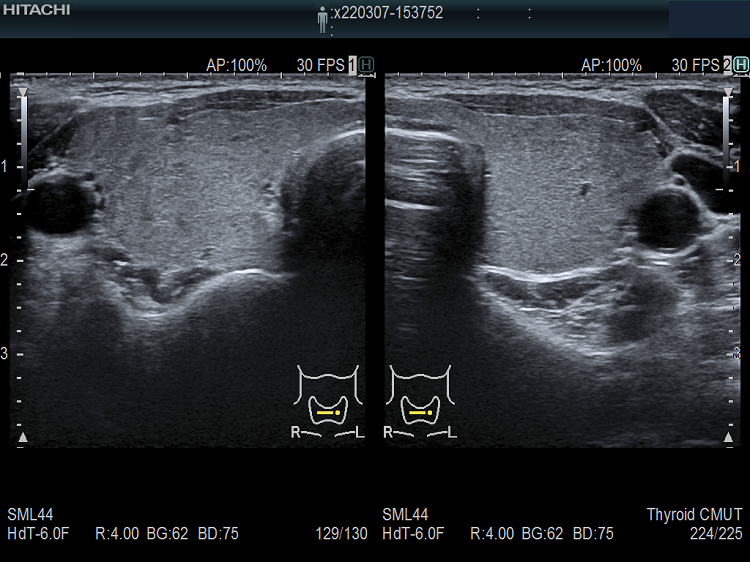

遺伝性甲状腺ホルモン合成障害で、サイログロブリン異常症(サイログロブリン遺伝子異常症)以外は、血中サイログロブリンが上昇するにも関わらず、甲状腺自体の破壊性変化に乏しく、マシュマロ様の軟らかい腺腫様甲状腺腫の形態を取る事があります。

ケース⑤

ケース⑥

遺伝性甲状腺ホルモン合成障害の超音波(エコー)画像は色々なパターンがあります。

- 常染色体優性遺伝型;腺腫様甲状腺腫の形態になります。